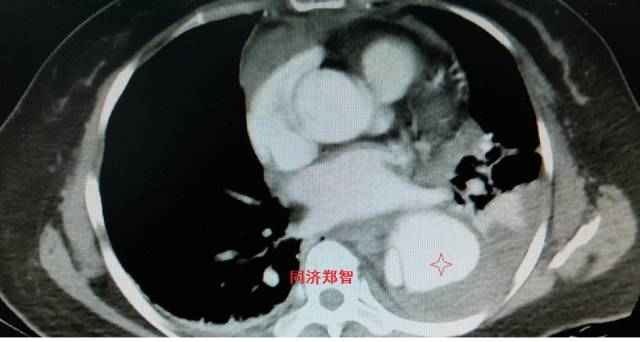

病例二

胸部平扫CT提示升主动脉增宽(红色星形标记),CTA证实A型主动脉夹层伴升主动脉夹层动脉瘤形成。